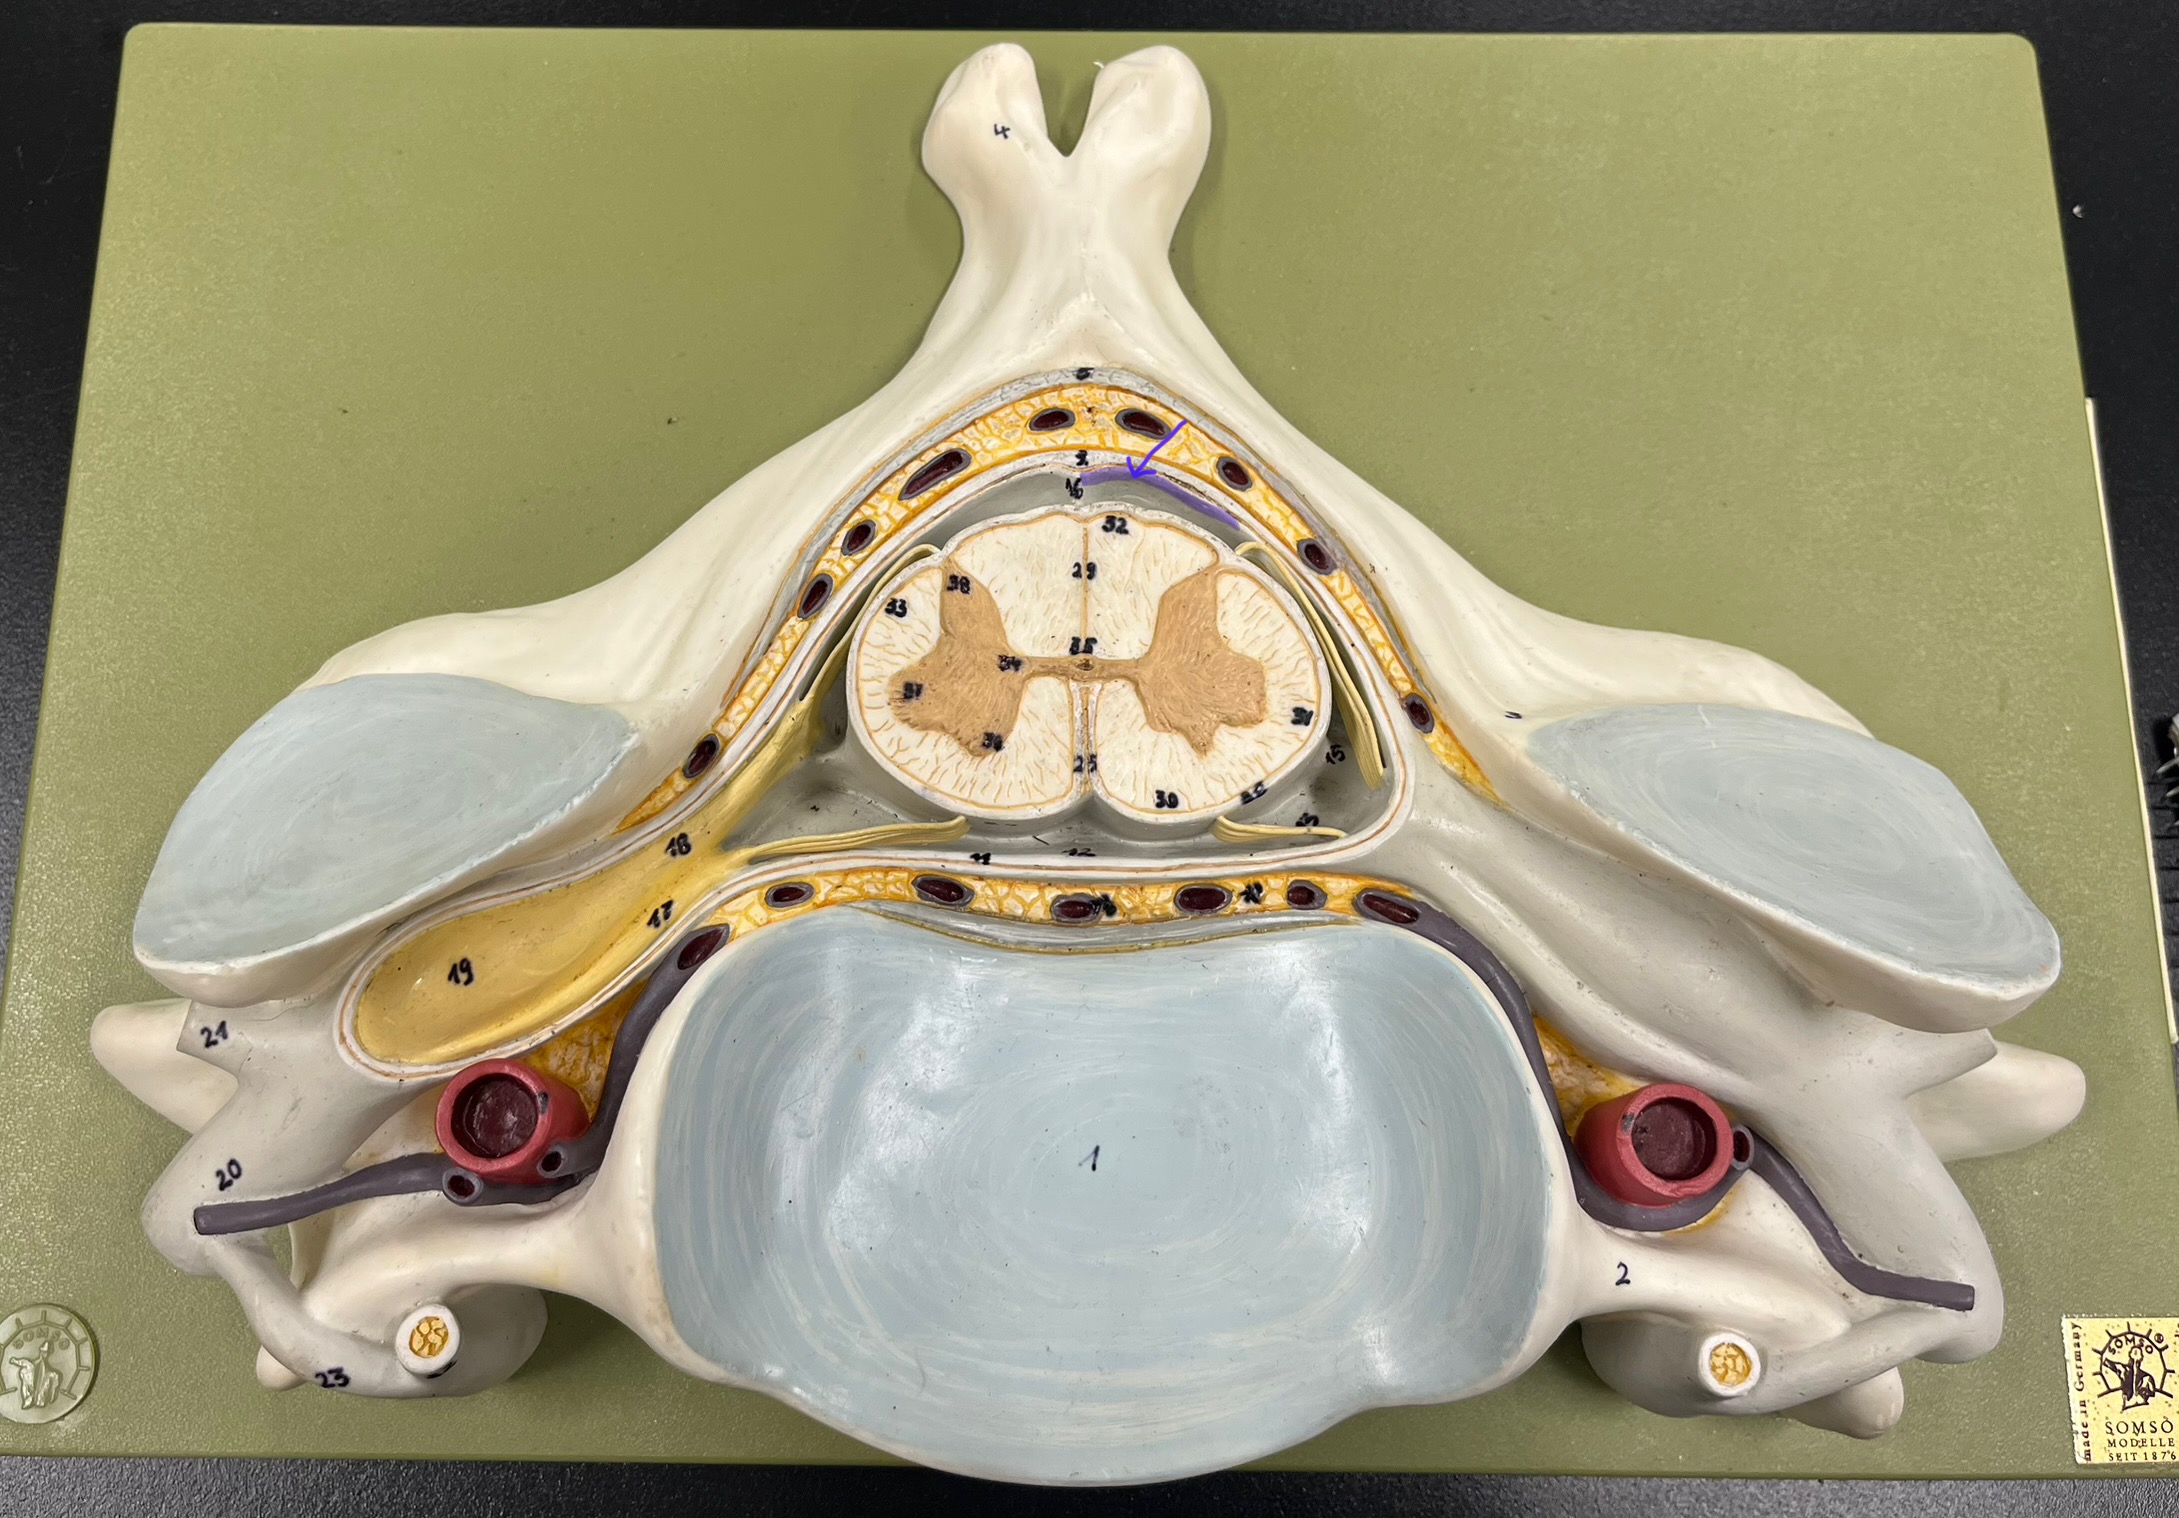

epidural space

dura mater

subdural space

arachnoid mater

subarachnoid space

pia mater

denticulate ligaments

What is the groove here?

anterior median fissure

posterior median sulcus

posterior (dorsal) horn

anterior (ventral) horn

lateral horn (selected models)

gray commissure

central canal

anterior column

lateral column

posterior column

white commissure

posterior (dorsal) root ganglion

What is the bulb here?

posterior (dorsal) root ganglion

posterior (dorsal) root

posterior (dorsal) root

anterior (ventral) root

anterior (ventral) root

dorsal ramus

dorsal ramus

ventral ramus

ventral ramus

rami communicantes

rami communicantes

sympathetic chain ganglia

sympathetic chain ganglia